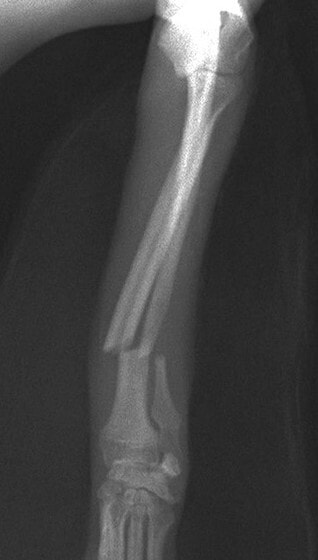

トイプードル 右遠位橈尺骨短斜骨折のALPSによる内固定

当院ではAdvanced Locking plate system(ALPS)と、Locking compression plate system(LCPS)という骨接合法で骨折症例の治療を行っています。

従来型のプレートのように広い面積で骨と接するプレートを用いて固定を行った場合、プレート下の骨はプレートとの接触面において血行が絶たれ壊死し、それがリモデリングされると骨密度が低下する。この骨密度の低下防ぐために、骨折部局所への血行を温存することの重要性が近年改めて認識されるようになってきている。Advaed Locking Plate System (ALPS)は従来型のプレートシステムの欠点を改良し、より使いやすく、より骨への血行を阻害しないようにというコンセプトで作られた。